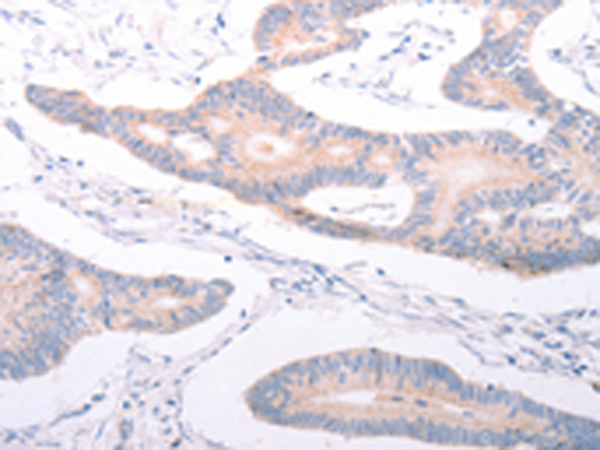

分类: 科研抗体货号: P11172别名:应用: IHC反应种属: Human, Mouse

分类: 科研抗体货号: P11170别名: PAQR2; ACDCR2应用: IHC反应种属: Human, Mouse

分类: 科研抗体货号: P11167别名: DSH; AGS6; G1P1; IFI4; P136; ADAR1; DRADA; DSRAD; IFI-4; K88DSRBP应用: IHC反应种属: Human

分类: 科研抗体货号: P11175别名:应用: IHC反应种属: Human

分类: 科研抗体货号: P11187别名: ANKRA应用: IHC反应种属: Human, Mouse

分类: 科研抗体货号: P11166别名: ADAM-TS6; ADAMTS-6; ADAM-TS 6应用: IHC反应种属: Human

分类: 科研抗体货号: P11174别名: AYTL3; AGPAT7; LPEAT2; LPAAT-eta应用: WB,IHC反应种属: Human, Mouse

分类: 科研抗体货号: P11186别名:应用: IHC反应种属: Human